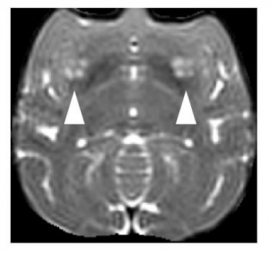

移植後のサルのMRI画像(矢印が細胞移植部分を示す)(写真: 京都大学 iPS細胞研究所の発表資料より)[写真拡大]

今回、パーキンソン病モデルの猿の脳に細胞を移植したところ、脳内に生着し機能していることが確認され、症状の軽減も認められた。さらに、移植してから少なくとも2年の間、腫瘍を形成することもなかった。この結果は、移植療法の有効性と安全性を示しているという。